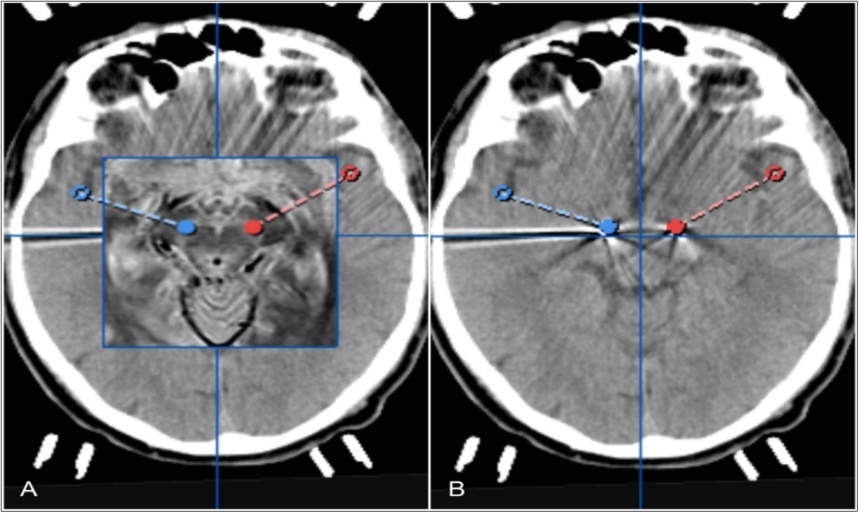

The procedure was performed without any complications. Postoperative cranial CT imaging revealed proper placement of both electrodes in the central part of STN (Figure 2). After fusion with the preoperative stereotactic plan, both electrodes were seen in the correct position of the STN (Figure 2). Electrodes were postoperatively activated bilaterally for continous stimulation with the wireless iOS mobile programming platform (Table 1). The patient experienced strong improvement of bradykinesia and rigidity under stimulation of the anterior segmented electrode (130Hz, 0.5mA). He was able to speak and walk without any problems. The apomorphin medication was stopped. L-dopa medication was reduced. Simultaneous activation of all segments around the circumference of the electrode caused the patient to suffer dysarthria and motor symptoms.

Figure 2.Pre- and postoperative computertomography merge showing tips of electrodes fused to bilateral trajectories of planned STNDBS